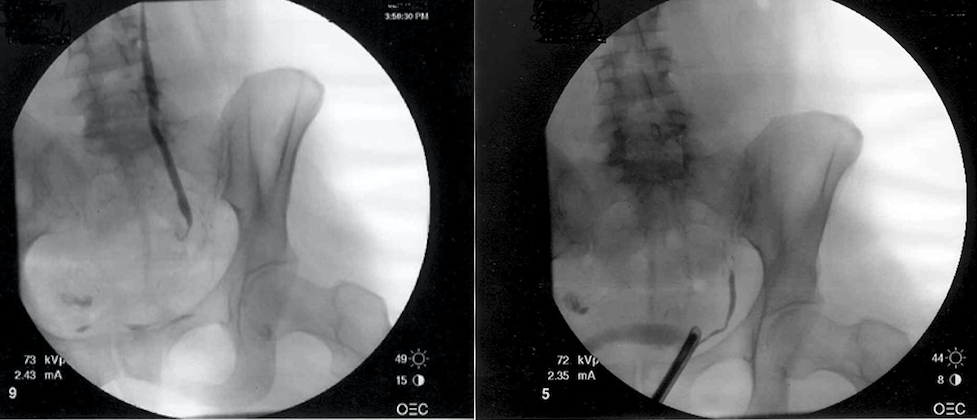

A 46-year-old woman sustained a ureteral injury during an abdominal hysterectomy for fibroids six weeks ago. A left percutaneous nephrostomy tube was placed. A retrograde ureterogram and an antegrade pyeloureterogram are shown. The next step is:

4

The retrograde and antegrade studies show a complete obstruction of the left distal ureter at the level of the uterine vessels. Most likely, the ureter was divided during clamping of the left uterine vascular pedicle or a thermal injury was sustained. The high grade obstruction (no contrast goes through the obstruction with both retro and antegrade injections) demonstrated makes the success of an endoscopic approach unlikely. Ureteroureterostomy is not a good option in the distal ureter, and should be reserved for short mid- to upper ureteral defects. The best repair for this patient is a ureteral reimplant with a psoas hitch. A Boari flap is not necessary in this patient and is reserved for lengthy distal ureteral defects up to 15 cm long.